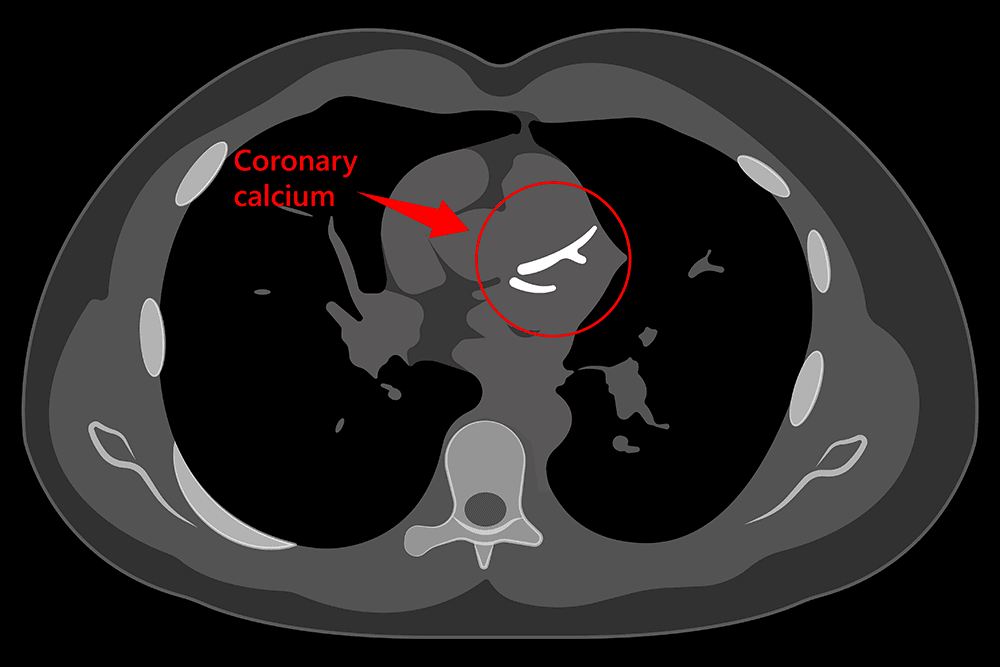

आपने अक्सर सुना होगा कि कैल्शियम हड्डियों के लिए बहुत अच्छा होता है, लेकिन क्या आप जानते हैं कि कैल्शियम हार्ट के लिए परेशानी का कारण बन सकता है। दरअसल ये कैल्शियम कोरोनरी आर्टीज (coronary arteries) में जम जाता है। जिससे वे संकरी और बंद हो जाती है। इसे प्लाक (Plaque) कहते हैं। प्लाक फैट, कैल्शियम और दूसरे तत्वों से मिलकर बनता है। ये लगातार अधिक मात्रा में जमा होने पर कोरोनरी आर्टरीज डिजीज (coronary artery disease) (CAD)  का कारण बन सकता है। जिसकी वजह से हार्ट अटैक आ सकता है। इस बिल्ड अप को डिटेक्ट करने के लिए डॉक्टर कैल्शियम स्कोरिंग टेस्ट (Calcium scoring test) का सहारा लेते हैं। इसे कोरोनरी आर्टरी कैल्शियम (CAC) स्कोरिंग, कोरोनरी कैल्शियम स्कैन, कैल्शियम स्कैन टेस्ट, कार्डिएक सीटी फॉर कैल्शियम स्कोरिंग जैसे नामों से जाना जाता है।

कैल्शियम स्कोरिंग टेस्ट के जरिए प्लाक के जमने का पता लगाया जाता है। इसे आप दांतों पर जमने वाले प्लाक की तरह ना समझें। यह आर्टरीज में अलग तरीके से पाया जाता है। शुरुआत में यह कोमल होता है और धीरे-धीरे इकठ्ठा होता है, लेकिन समय के साथ यह सख्त होता जाता है। डॉक्टर इसे कैल्सीफाइड प्लाक (calcified plaque) भी कहते हैं। यह निम्न दो कारणों के चलते परेशानी का कारण बन जाता है।

• कैल्शियम स्कोरिंग टेस्ट के जरिए ये पता लगाया जाता है कि कितना प्लाक हार्ट आर्टरीज में जमा हो गया है। डॉक्टर रिजल्ट देखने के बाद ट्रीटमेंट के बारे में निर्णय लेते हैं।